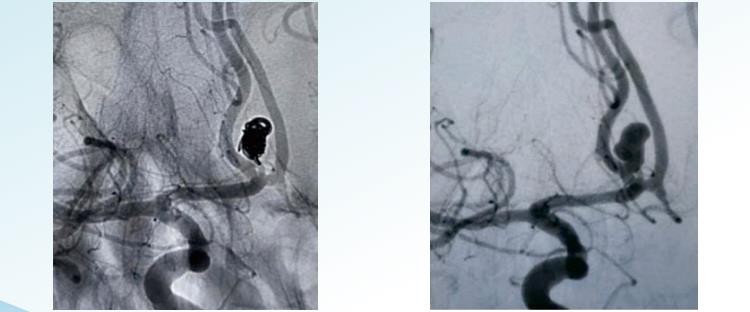

RenovaTMaftengjanlegt slagæðagúlpskerfi býður upp á handahófskenndan, þyrillaga og þrívíddarlausan möguleika fyrir æðablóðrek í þvermál frá 1 til 22 m. Hann er hannaður til að embocera æðagúl frá ramma til enda og inniheldur vafninga sem eru sérstaklega lagaðir til að ná sammiðja fyllingu æðagúls og vafningum af miklu rúmmáli til að ná háum pökkunarþéttleika. Tilviljunarkennd vafning er einfaldasta og elsta form æðagúlpsvólunartækni. Það felur í sér að stakur spóla eða hópur spóla er settur inn í slagæðagúlpinn. Spólurnar eru venjulega gerðar úr platínu og eru þunnar og þétt spólaðar til að koma í veg fyrir að eyður eða bil myndist í sekknum. Hringlaga vafning felur í sér notkun á lengri, þunnum vír sem er spólaður um sjálfan sig á þyrillaga hátt og myndar gorma-líka byggingu. Vírinn er settur inn í slagæðagúlpinn í réttu formi og þegar hann er kominn inn er hann látinn spóla og þenjast út til að fylla slagæðapokann. Helical spólur eru breiðari og meira pakkaðar en tilviljunarkenndar spólur og veita þannig betri lokun æðagúlsins. 3D spólan felur í sér notkun sérsniðinna-hönnuða spólu, sem er framleidd með tölvutæku myndferli sem býr til nákvæmt þrívíddarlíkan af slagæðagúlpinu. Spólan er framleidd til að passa nákvæmlega stærð og lögun æðagúlsins. Þessi tegund af spólu er hönnuð til að passa vel inn í slagæðagúlpinn, veita framúrskarandi lokun og draga úr hættu á fylgikvillum. 3D spólur eru sérstaklega áhrifaríkar við að meðhöndla slagæðagúlp sem erfitt er að ná til eða í viðkvæmum æðum.

RenovaTM3D aftengjanlegar spólur

RenovaTMSpóla sem hægt er að taka af með þyrlum